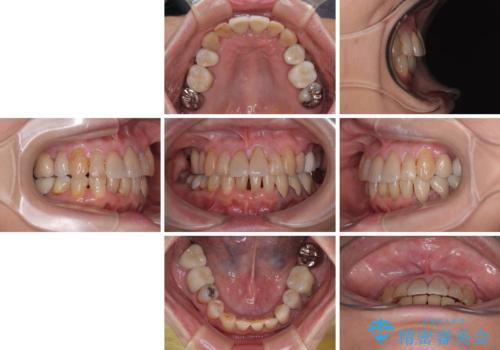

歯肉移植などによる前歯部の歯肉ライン改善を提案しましたが、口を開けたときにほとんど見えないので気にならないとのことで、特に処置を行うことなく補綴治療を行いました。